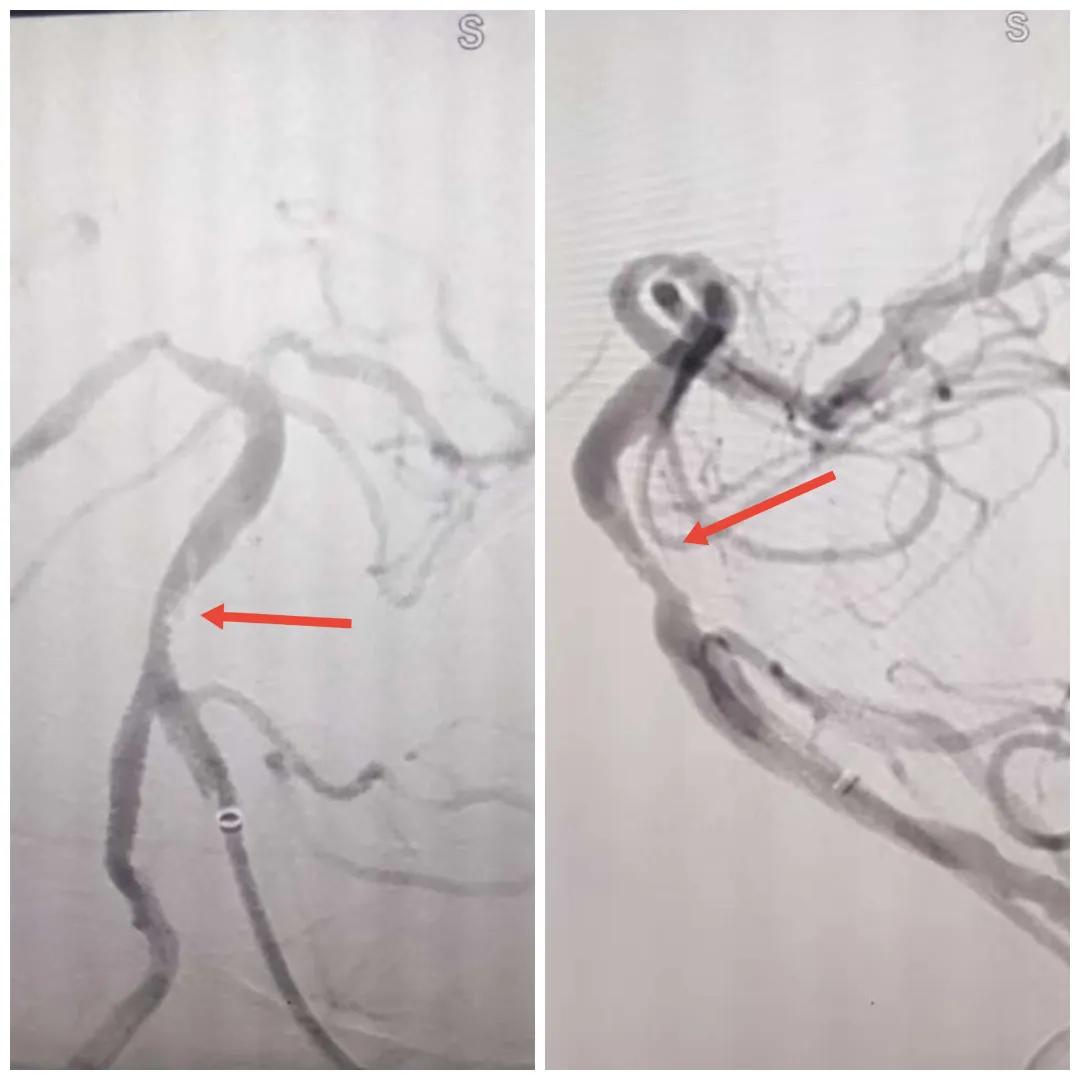

在經(jīng)造影后,主刀醫(yī)生腦一科副主任楊慶堂發(fā)現(xiàn)患者基底動脈下段重度狹窄且狹窄段以遠(yuǎn)有大負(fù)荷血栓,其狹窄處考慮為動脈夾層,手術(shù)難度及風(fēng)險(xiǎn)較大。楊慶堂副主任在彭壯副主任醫(yī)師的協(xié)助下運(yùn)用spaceman(太空人)技術(shù),中間導(dǎo)管抵近血栓抽吸配合支架拉栓,成功開通血管。再次造影可見基底動脈管腔明顯增寬,遠(yuǎn)端血管顯影良好,且等待20分鐘后造影仍顯示血流通暢。楊慶堂副主任考慮到本次手術(shù)時(shí)間不宜過長,現(xiàn)患者基底動脈及分支前向血流維持良好,給予其抗栓藥物應(yīng)用后結(jié)束手術(shù),并建議患者3個(gè)月后復(fù)查造影,明確其基底動脈夾層情況。

造影可見血管夾層和大量血栓形成

取栓后血管管腔增寬,前向血流良好